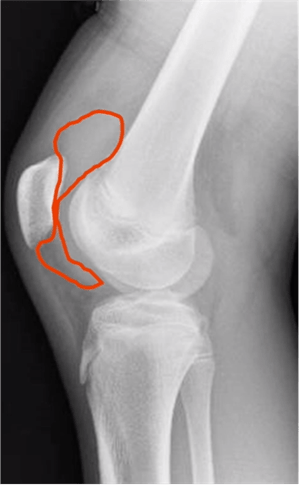

- X-ray – side view image of the knee

- Look at the kneecap as it is related to the thigh bone.

- Look at the muscle coming off the kneecap

- Look at the space between the kneecap and the femur

- If there is a curvilinear density that is not the linear muscle, not the deep muscle or the fat pad, it is most likely an effusion.

OCD is an idiopathic osteonecrosis below the cartilage surface during development. This can lead to cartilage surface cracks, instability and lesion on the joint. OCD can happen with or without trauma. In an X-ray, a radiolucent lesion is visible.